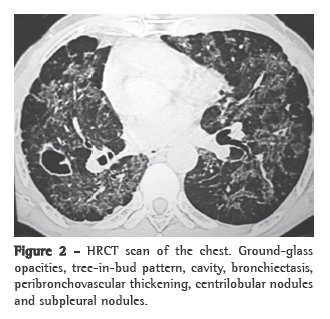

A simple chest X-ray (Figure 1) can reveal asymmetric reticulonodular infiltrate, predominantly in the two upper thirds of both lungs, accompanied by hypertransparent areas at the lung bases.(1,2,4)